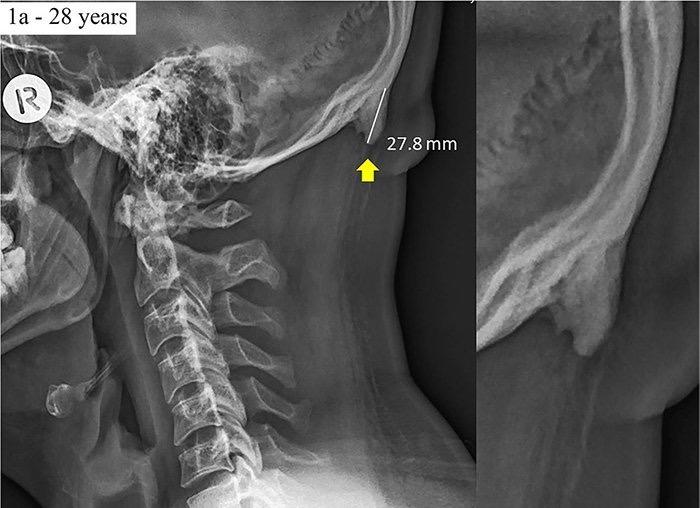

豪サンシャインコースト大学のデビッド・シャハル博士らの研究チームは、18歳から30歳までの若者218名を対象に外側頸部のレントゲン写真を分析し、2016年3月22日、学術雑誌「ジャーナル・オブ・アナトミー」でその成果を発表した。

これによると、被験者のうちの41%に外後頭隆起の突出が認められ、10%は20ミリ以上の外後頭隆起が認められた。外後頭隆起の突出は、女性よりも男性に多く認められ、中には、その大きさが35.7ミリに達するものもあった。なお、ヒトの外後頭隆起は通常5ミリ程度で、10ミリを超えると大きいとされている。

さらに、シャハル博士らの研究チームは、18歳から86歳までの1200名を対象に、年齢や性別、前かがみ姿勢の角度と外後頭隆起の突出との関連についても分析した。科学誌「サイエンティフィック・リポーツ」で2018年に掲載された研究論文によると、被験者のうち33%に外後頭隆起の突出が認められ、男性のほうが外後頭隆起の突出が多く、前かがみ姿勢の角度が大きいほど、外後頭隆起の突出が起こりやすいこともわかった。また、仮説に反して、年齢が高くなるほど、外後頭隆起の突出が起こりにくいことも示されている。